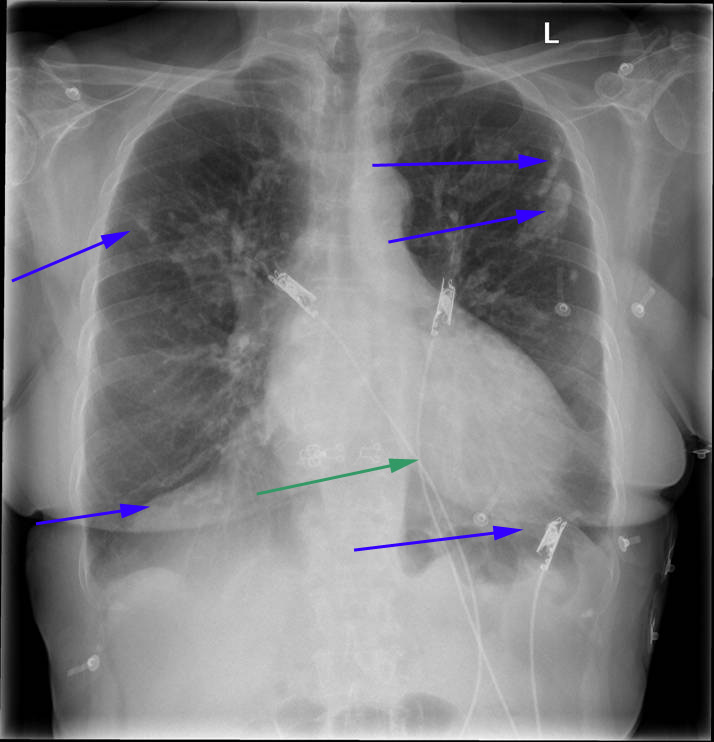

A: Røntgenundersøgelse af thorax. På den første optagelse (A- ovenfor) ser man en del forkalkninger i lungehinderne (blå pile) som skyldes, at patienten har været udsat for asbest. Metaltrådene (grøn pil) er EKG-elektroder.